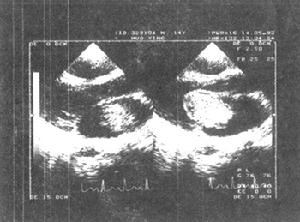

4.超聲心動圖左房粘液瘤在左心腔內見到異常的點片狀反射光團,活動於左房、左室之間,收縮期回到左房腔,舒張期達二尖瓣口進入左室,二尖瓣前葉EF斜率減低,左房增大。右房粘液瘤異常反射光團在右心腔內,收縮期在右房,舒張期隨三尖瓣向右室方向移動或通過三尖瓣口進入右室腔。右房、右室增大。

3.超聲心動圖檢查顯示瘤體隨心臟收縮和舒張活動。心血管造影顯示心腔內占位性病變,但有一定的假陽性、自有超聲心動圖,心血管造影較少套用。